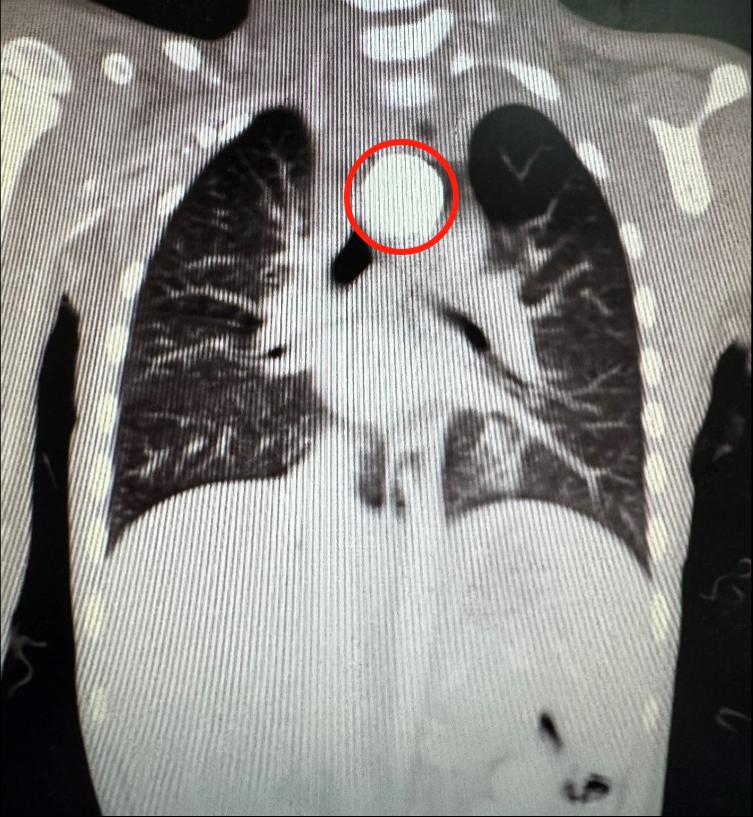

4岁的小雨(化名)出于好奇,将一枚纽扣电池吞进了肚子,家人却浑然不知。三天后,孩子突然剧烈呕吐、高烧不退,送当地医院检查才惊觉真相:纽扣电池死死卡在食管胸上段,紧邻气管与大动脉(主动脉)!此时,电池强腐蚀性电解液已开始“啃噬”周围组织,形成溃疡。

当地医院尝试经胃镜取物,但因食管腔内异物周围已形成溃疡,难以取出。命悬一线之际,小雨被紧急转至珠江医院儿童重症医学科(PICU)。医院火速启动多学科联合救治——胸外科、小儿外科、消化内科、麻醉科专家齐集手术室。预案双线并行:内镜团队全力取物,胸外科团队随时准备开胸手术!

消化内科唐银丽医生在胃镜下发现,电池周围组织已严重水肿、灼伤溃烂,万幸尚未穿孔。经过精密操作,腐蚀性电池终被取出!“再晚一步,穿孔腐蚀大血管,后果不堪设想!”PICU副主任医师金明心有余悸。